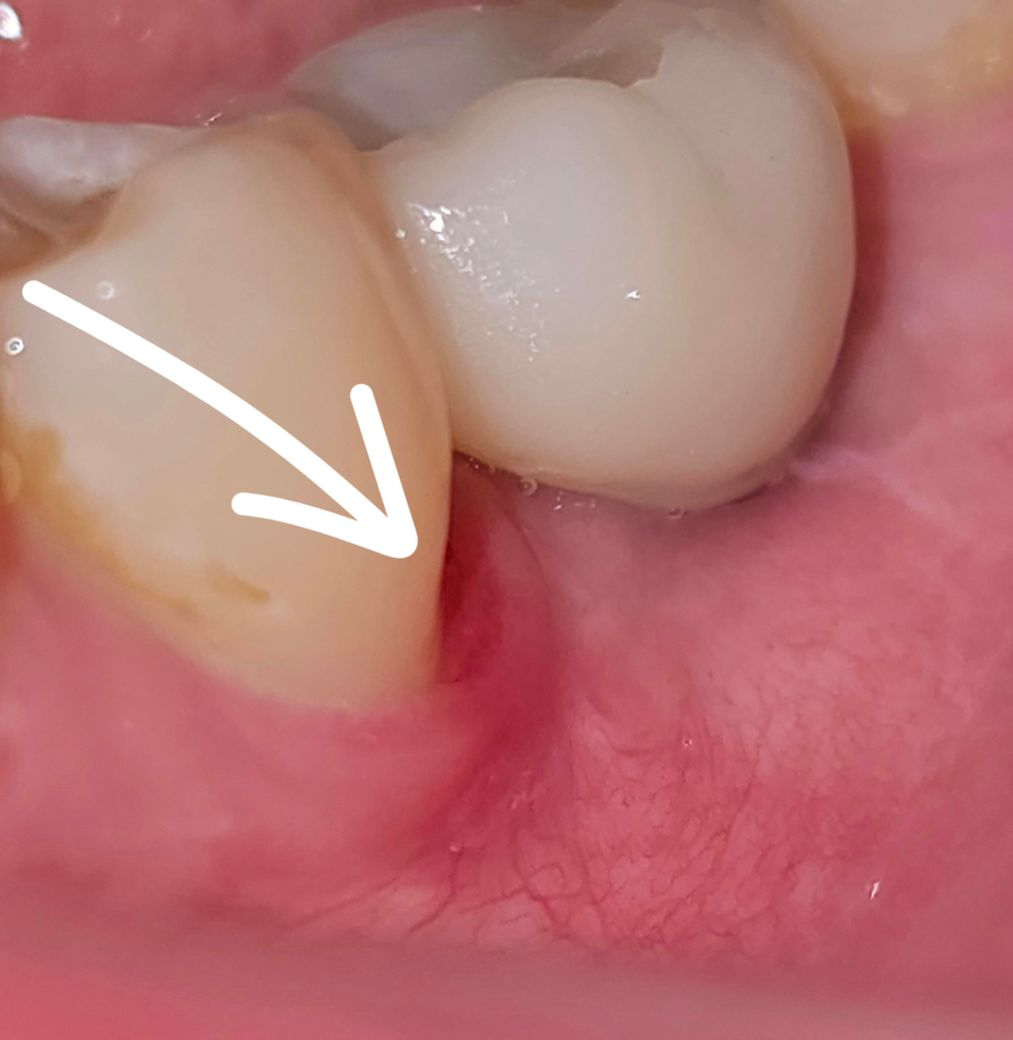

<3주 뒤>

3주 째인데 전혀 낫지않고 상처 부분이 그대로 또는 오히려 더 커지는 것 같아요.

약간 궤양? 같기도하고 생긴게 상처난 피부가 염증으로 물러진 것 처럼 생겼습니다.

닦으면 피가 뭍어 나옵니다.